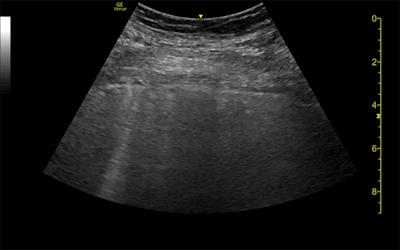

Ultrasound and CT images from a 62-year-old woman with long-term COVID-19 symptoms. The patient, who was not part of the study, visited the Madrid emergency department with persistent dyspnea and cough. The ultrasound image (above) shows an irregular pleural line and some B-lines, which correlate to ground-glass opacities in the lower lobes on CT (below). Images courtesy of Dr. Yale Tung-Chen, PhD.

The three patients in the study, which was published in the Journal of Ultrasound in Medicine, had mild cases of COVID-19 but lingering shortness of breath. Ultrasound scans revealed a variety of pulmonary findings, including irregular pleural lines and B-lines, which correlated with abnormalities on CT scans.

- The 35-year-old woman had a mild, irregular pleural line and B-lines in her right anterior chest on ultrasound, which correlated with ground-glass opacities on CT.

However, ultrasound has its own drawbacks, notably limited sensitivity. This was especially evident in the case of the 35-year-old woman whose mild irregular pleural line on ultrasound corresponded not to abnormal pleura on CT but parenchymal tissue changes.